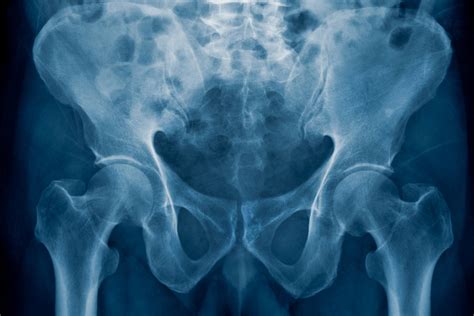

Normal Hip X Rays are a type of radiographic imaging used to visualize the hip joint and surrounding structures. This non-invasive procedure helps diagnose a wide range of conditions, including fractures, dislocations, arthritis, and developmental issues. The hip joint is a complex structure composed of the femoral head, acetabulum, and supporting ligaments and muscles. Normal Hip X Rays provide a clear view of these components, aiding in accurate diagnosis and treatment planning.

Interpreting Normal Hip X Rays requires a trained eye and a thorough understanding of hip anatomy. Radiologists look for specific features and measurements to determine the health of the hip joint. Key areas of focus include:

• Bone Density: Normal bone density indicates healthy bone structure. Any areas of decreased density may suggest osteoporosis or other bone diseases.

• Joint Space: The space between the femoral head and the acetabulum should be uniform and well-defined. Narrowing of this space can indicate arthritis or other degenerative conditions.

• Alignment: Proper alignment of the femoral head within the acetabulum is crucial. Misalignment can suggest dislocations, fractures, or developmental issues.

• Soft Tissue: While X-rays primarily focus on bone structures, they can also reveal abnormalities in soft tissues, such as swelling or calcification.